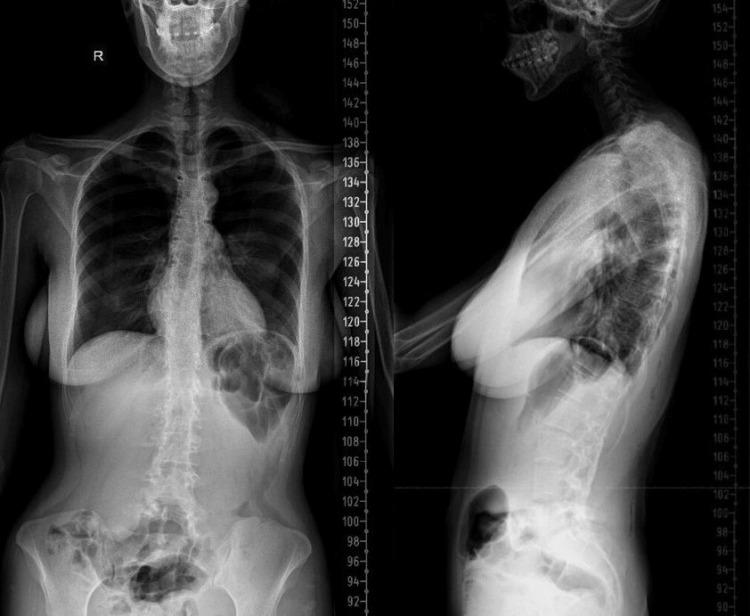

This case report presents the case of a 22-year-old female patient with a history of adolescent idiopathic scoliosis who underwent posterior spinal fusion and instrumentation from T4 to L5 at age 17. Her postoperative course was uneventful for five years, during which she remained asymptomatic and functionally independent. At age 22, she developed insidious axial low back pain without trauma or neurological symptoms. Imaging revealed a right L5 pedicle fracture with no evidence of implant loosening or pseudoarthrosis. Conservative management, including nonsteroidal anti-inflammatory drugs (NSAIDs), local injections, and physical therapy, failed to relieve symptoms. A CT scan confirmed solid fusion and an isolated pedicle fracture. Surgical removal of the instrumentation was performed, followed by application of a thoracolumbar orthosis. The patient returned to full daily activities without pain by one year postoperatively. This case highlights a rare complication of distal pedicle stress fracture after long-segment fusion, emphasizing the need for awareness of junctional stress-related pathology in long-term follow-up and the effectiveness of timely surgical management.

本病例报告介绍了一名22岁女性患者,该患者有青少年特发性脊柱侧弯病史,17岁时接受了从T4至L5的后路脊柱融合及内固定术。术后五年她的病程平稳,在此期间她没有症状,功能独立。22岁时,她在没有外伤或神经症状的情况下逐渐出现隐匿性轴向腰背痛。影像学检查显示L5右侧椎弓根骨折,没有植入物松动或假关节形成的迹象。包括非甾体类抗炎药(NSAIDs)、局部注射和物理治疗在内的保守治疗未能缓解症状。CT扫描证实融合良好且为孤立性椎弓根骨折。遂进行了内固定器械的手术取出,随后应用了胸腰骶矫形器。术后一年,患者恢复了全部日常活动且无疼痛。本病例突出了长节段融合后远端椎弓根应力性骨折这一罕见并发症,强调了在长期随访中需要关注交界区应力相关病变以及及时手术治疗的有效性。